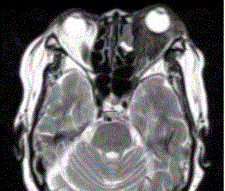

患者女,64岁,左眼突出5年余。查体左眼球前突6mm,眼球运动自如,眼底无异常,下睑扪及边界不清、质软的肿块,视力正常,MR表现如下图。临床拟...

问题 患者女,64岁,左眼突出5年余。查体左眼球前突6mm,眼球运动自如,眼底无异常,下睑扪及边界不清、质软的肿块,视力正常,MR表现如下图。 临床拟诊为

选项 A.眶内炎性假瘤 B.眼型Grave病 C.黑色素瘤 D.转移瘤 E.眼眶海绵状血管瘤 F.弥漫型淋巴管瘤

答案 A